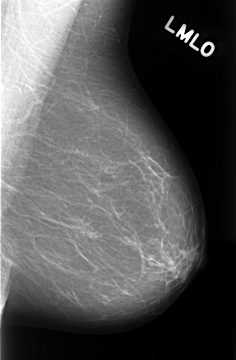

C_0319_1.LEFT_MLO

LEFT_MLO LINES 4312 PIXELS_PER_LINE 2832 BITS_PER_PIXEL 12 RESOLUTION 50 NON_OVERLAY